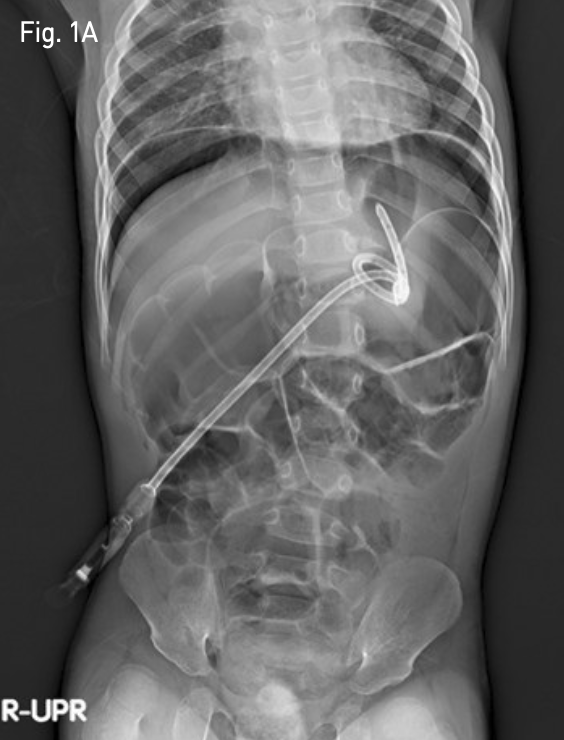

Fig. 2A

A fluoroscopic image shows significant distance between first inserted T-fastener (white arrow) and second inserted T-fastener (open arrow).

먼저 0.035-inch guide wire(Terumo, Tokyo, Japan)를 이미 거치되어 있던 12-Fr 위창냄술 튜브 (Cook, Bloomington, IN, USA)내로 진입시킨 후 제거하였다. 이후 신속히 4-Fr sheath(Cook, Bloomington, IN, USA)를 거치한 후 두 번째 T-fastener를 삽입하였고 적절한 힘으로 앞 복벽에 밀착시켰다. 이후 제시하였던 12-Fr 위창냄술 튜브(Cook, Bloomington, IN, USA)를 다시 삽입한 후 마지막으로 T자형 고정장치와 튜브를 피부에 고정하였다. 투시 장비로 측면상을 보았을 때, 첫번째 삽입하였던 T-fastener와 새로이 삽입한 T-fastener 간에 상당한 차이가 있음과, C-arm CT상 전복벽에 위전벽이 완전히 밀착되었음을 확인하였다(Fig. 2A-B). 조영제를 주입하여 튜브의 기능과 조영제의 복강내로 유출이 없음을 확인하였다.